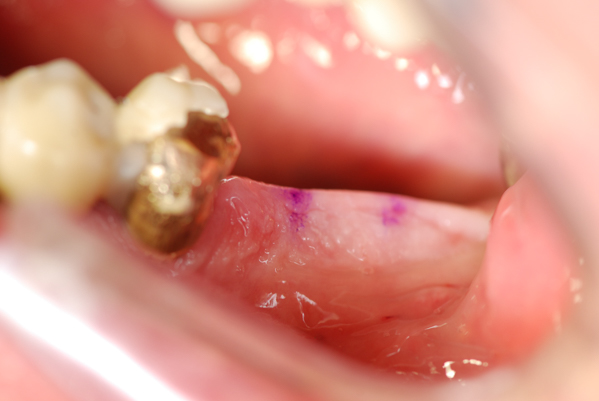

Ein minimalinvasives Zahnimplantat benötigt nur ein sehr kleine Bohrung und kommt ohne Schnitte und damit fast ohne Schmerz aus, so wie in diesem Fallbeispiel gezeigt wird. Mehr muss nicht sein, das Aufklappen mit Schnitten wie es früher üblich war führt zu Schmerz und dauert lange um Abzuheilen mimi-info.de. Wann und wie eigenen sich Sofortimplantate ? Bei einer minimalinvasiven OP wird das Zahnfleisch nicht geschnitten und vom Knochen abgelöst wie in der klassischen Implantologie. Durch eine 3D Röntgenaufnahme und durch den Tastsinn und die Erfahrung eines Implantologen oder auch zu Hilfenahme von Robodent ist es möglich durch die Haut hindurch zu implantieren.

Das Zahnimplantatbett wird durch Verdichtung des Kieferknochens gewonnen .

Dabei kommt ein Knochenverdichter zum Einsatz der den wertvollen Knochen nicht abspänt sondern nur zur Seite drängt also verdichtet um den Knochen zur schnelleren Belastung vorzubereiten. Minimalinvasives Sofortimplantation im Selbstversuch. Bereits 2010 hat mein Kollege Herr Forster das erste Sofortimplantat in unserer Zahnarztpraxis bei mir selbst (Dr. Junk Bernard) erfolgreich und schmerzarm eingesetzt. Ich beiße heute noch jeden Tag damit. Aus diesem ganz persönlichen positiven Erfahrungen empfehle ich es auch meinen Patienten. Mittlerweile wurden bei Zahnarzt München ca. 10.000 Sofortimplantate gesetzt, fast alle ohne Komplikationen. Wer sich dafür mehr interessiert, sollte meinen Bericht darüber unter http://mundgesund.eu anklicken.

Kleine Bohrung, blutarm, schmerzarm ohne Schwellungen Knochenverlust - preiswert minimalinvasive Sofortimplantate beim Zahnarzt Dr. Junk in München